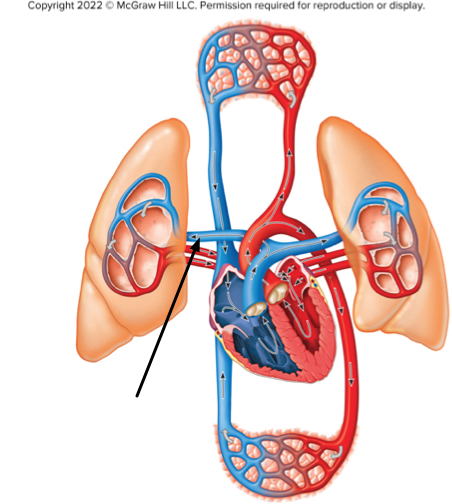

The structure at the tip of the arrow contains

deoxygenated blood of the pulmonary circuit